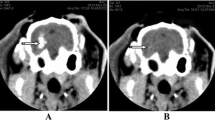

The anesthetized rabbit was fastened to the stereotaxic apparatus, and the skin in the operation field was disinfected using 75% alcohol. A 3-cm incision was made along the mid-line at the line of connection between the two post-orbital margins, and the skull was stripped of subcutaneous fascia to expose the skull. A 3% H2O2 solution was used to open the periosteum and expose the bregma and lambdoid sutures. The head was then adjusted to make the bregma 1.5 mm higher than the lambdoid suture. The position of the internal capsule was located according to the rabbit stereotaxic atlas. The coronal plane crossing the center of bregma was used as the coronal zero plane (AP0), A1 represented the coronal plane 1 mm ahead of AP0 and the internal capsule was estimated to be between A5 and P2. The present experiment used the A1 level and the bregma as base points, using 6 mm left along the coronal suture and 1 mm parallel to the sagittal suture as the puncture point. The skull of the rabbit was drilled, and using a #12 needle and a 1-ml syringe, 0.8 ml autologous arterial blood was taken from the central ear artery. The syringe was then connected to a #7 needle in which the tip was removed. Air was completely removed from the syringe, leaving 0.5 ml of blood. The #7 needle was then inserted vertically and quickly into the skull 12 mm deep, and the blood was slowly injected into the basal ganglia. The injection lasted for approximately 3 min. The needle was left in place for 8 min after the blood was injected to prevent the backflow of the blood, and then the needle was pulled out slowly. Local hemostasis was induced by compression for 2 min. The drill hole was then covered using gutta-percha. A CT scan was performed 3 h later. A high-density shadow in the basal ganglia region with no shadow in the lateral ventricle was considered successful ICH induction (Fig. 1a).

Brain CT showing the area of the intracerebral hematoma before and after evacuation. a Brain CT 3 h after the induction of ICH. The round, high-density shadow in the left basal ganglia region demonstrated the successful induction of the hematoma. b The hematoma in the left basal ganglia region was removed using a minimally invasive procedure, and the high-density shadow disappeared

The rabbits were anesthetized again by injecting 20% urethane (5 ml/kg) into the ear vein. They were then placed in the stereotaxic apparatus, and the skin over the operation field was disinfected using 75% alcohol. Using the former drill hole, a #7 needle was inserted into the hematoma, and the liquid part of the hematoma was aspirated. We then injected 5,000 U of urokinase (dissolved in 0.5 ml of 0,9% sodium chloride solution) into the hematoma. The needle was kept in place for 15 min, followed by slow aspiration while withdrawing the needle. A CT scan was performed again, and the high-density shadow was mostly removed (Fig. 1b). The drill hole was then covered using gutta-percha. The skin around the area was disinfected and finally sutured. The rabbits were then placed back in the breeding room for 1, 3, or 7 days.